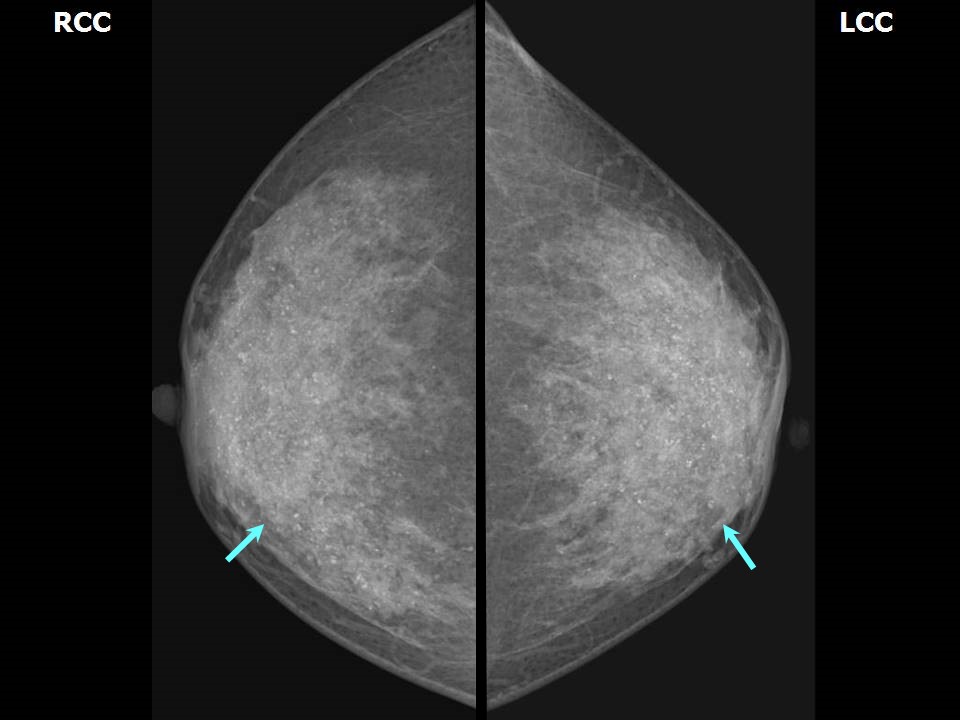

From whri.org

What should you know about breast density? Breast Cancer Awareness What Do Calcium Deposits In Breast Mean Breast calcifications are calcium deposits within breast tissue. Often not cancerous, breast calcifications are detected on mammograms. They are very common and are usually benign (noncancerous). They appear as white spots or flecks on a mammogram. Breast calcifications are small pieces of calcium deposited into breast tissue and are very common. Breast calcifications are small calcium deposits that develop in. What Do Calcium Deposits In Breast Mean.